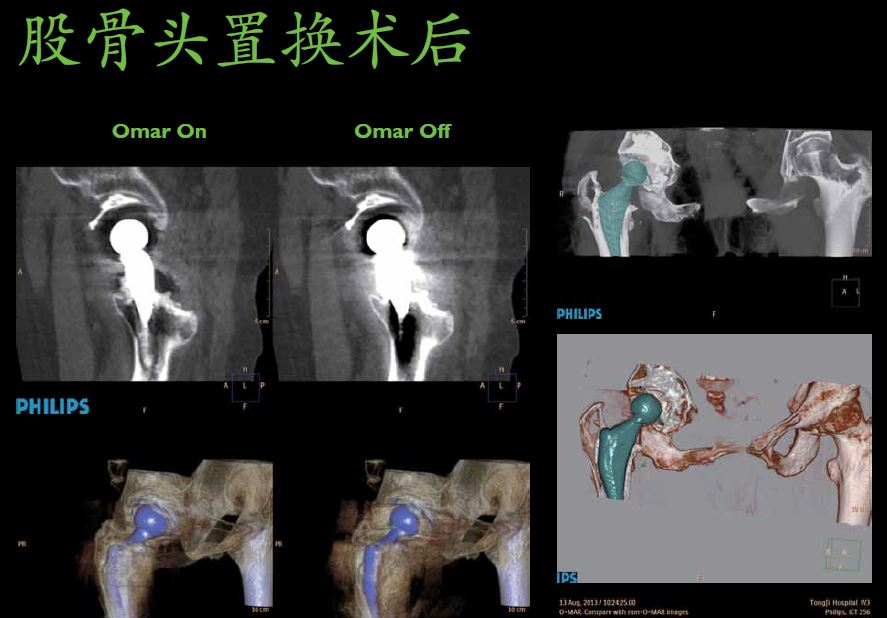

显微成像——动态四焦点及纳米探测器实现4800采样/0.27秒最高采样率,丰富信息成就1024x1024超高分辨成像技术,4倍信息量提升令微小病灶诊断不再困惑。同时高效的祛金属伪影O-Mar功能防止漏诊情况。

O-Mar可以有效祛除金属伪影,保证有效的还原原有的图像